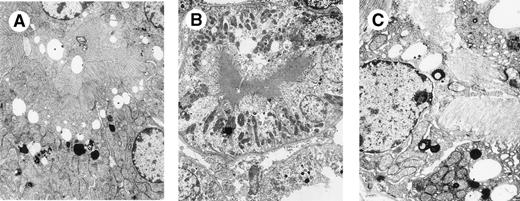

Mutant CHEB mice and 269 mice kidneys. (A) MouseCHEBm30 no. 1, kidney, electron microscopy (original magnification × 6,000). (B) Mouse CHEBm94 no. 1, kidney, electron microscopy (original magnification × 2,500). (C) Mouse 269 no. 10, kidney, electron microscopy (original magnification × 4,000): moderate or heavy increase of lysosomal component in proximal tubular cells with variable apical vacuolation secondary to reabsorption of mutated CHEB or 269 LCs. Crystalline inclusions are absent in the lysosomal compartment.

A high secretion rate of human κ chain was observed in vitro after transfection of Sp2/0 hybridoma cells with cDNA expression vectors encoding either the FS κI chain CHEB, the control κI chain 269, the 2 mutated CHEB chains (CHEBm30 andCHEBm94), or the mutated 269m30 chain. The mutated CHEBchains did not differ from the original CHEB κ chain in their apparent molecular mass in PAGE-SDS or in their ability to polymerize as dimers and tetramers (Fig 2A and B). In vivo, human κ chains were produced in mice injected with these transfected clones (Table1), but not in control mice injected with untransfected Sp2/0 cells (C mice; not shown). In C mice, kidneys were normal. In 7 of 10 CHEB mice, light microscopy examination of kidney samples showed marked proximal tubular cell lesions with clear cytoplasmic atrophy and numerous intracellular crystals; toluidine blue typically stained multiple rhomboid crystals within a large number of proximal tubular cells (Fig 3A). Rarely (2 of 10 mice) were crystals found in the tubular lumens, but no myeloma casts were found. By immunofluorescence, these intracellular crystals strongly stained with an antihuman κ chain (Fig 3B). Electron microscopic analysis of proximal tubular cells of CHEB mice showed that inclusions in proximal tubular cells were surrounded by smooth membranes and were located predominantly in the apical pole of cells (Fig 3C) and also confirmed the crystalline nature of the hexagonal inclusions with a regular striation of 60 Å periodicity (Fig 3D). By immunoelectronmicroscopy, these crystals were stained with antihuman κ chain, anticathepsin D sera, and protein L (which specifically binds Vκ domains). The results observed with CHEB mice were very similar to those observed in patient CHEB, either by immunofluorescence labeling pattern with the antihuman κ chain (Fig 4A) or by electronmicroscopic examination of intracellular crystals (Fig 4B and C). Transfected hybridoma cells themselves producing the CHEB κ chain did not contain any intracytoplasmic crystalline inclusions (data not shown). Similar analysis on kidney biopsies from CHEBm30 andCHEBm94 mice did not show crystals in tubular cells (Fig 5A and B), but only cytoplasmic droplets indicating internalization of the chain by the normal process of proximal tubular reabsorption (9 of 9 and 7 of 7, respectively).

Finally, in κI 269 control mice, the proximal tubular cells contained droplets (8 of 10) and were sometimes atrophic, but no crystal inclusions were found (Fig 5C). Surprisingly, large tubular myeloma casts were found in 5 of 10 269 mice (Fig6A), which strongly stained with antihuman κ conjugate (Fig 6B and C). The same pattern was observed in mice expressing the mutant 269m30 of the control 269 chain, with myeloma casts in 4 of 8 mice and no crystals (Table 1). Interestingly, CHEBm30 κ chains, sharing both Ser30 and Ile94 residues with 269 LC, also led to the formation of myeloma casts in 2 injected mice (no. 1 and 9 in Table 1).